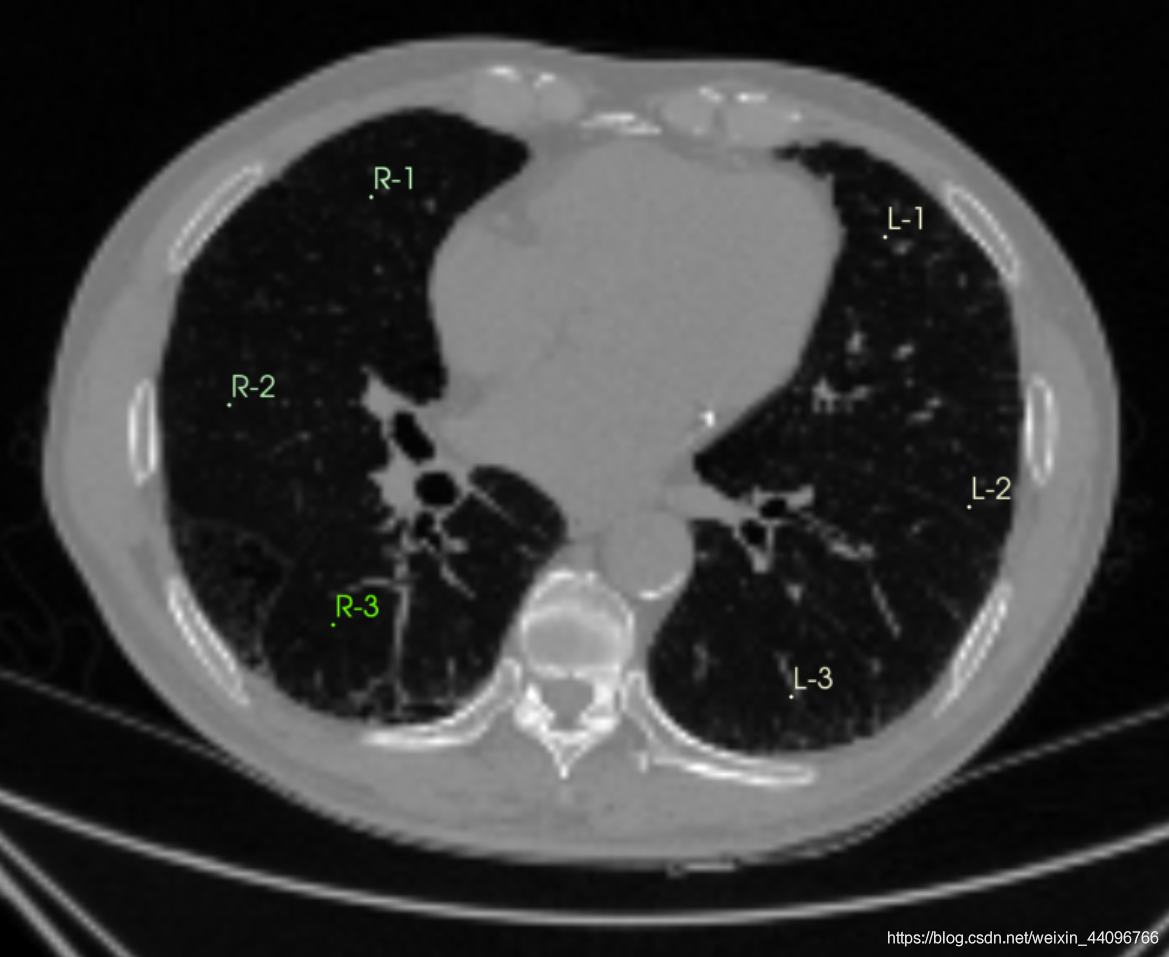

肺部分割

- 进入插件

- 点击start,根据提示在左、右肺、气管处标点后点击apply

分割出来的区域可以根据需要在Segment Editor中手动调整。